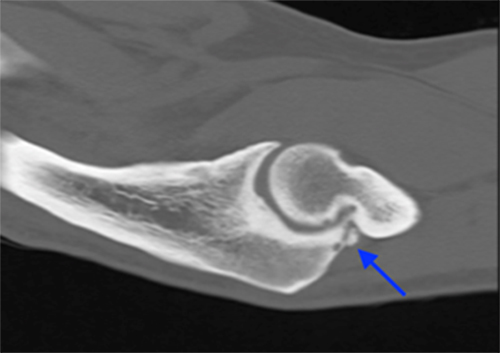

- CT scan is best for identifying loose bodies and osteophytes for surgical planning

CT scan demonstrates posteromedial osteophytes within the olecranon fossa